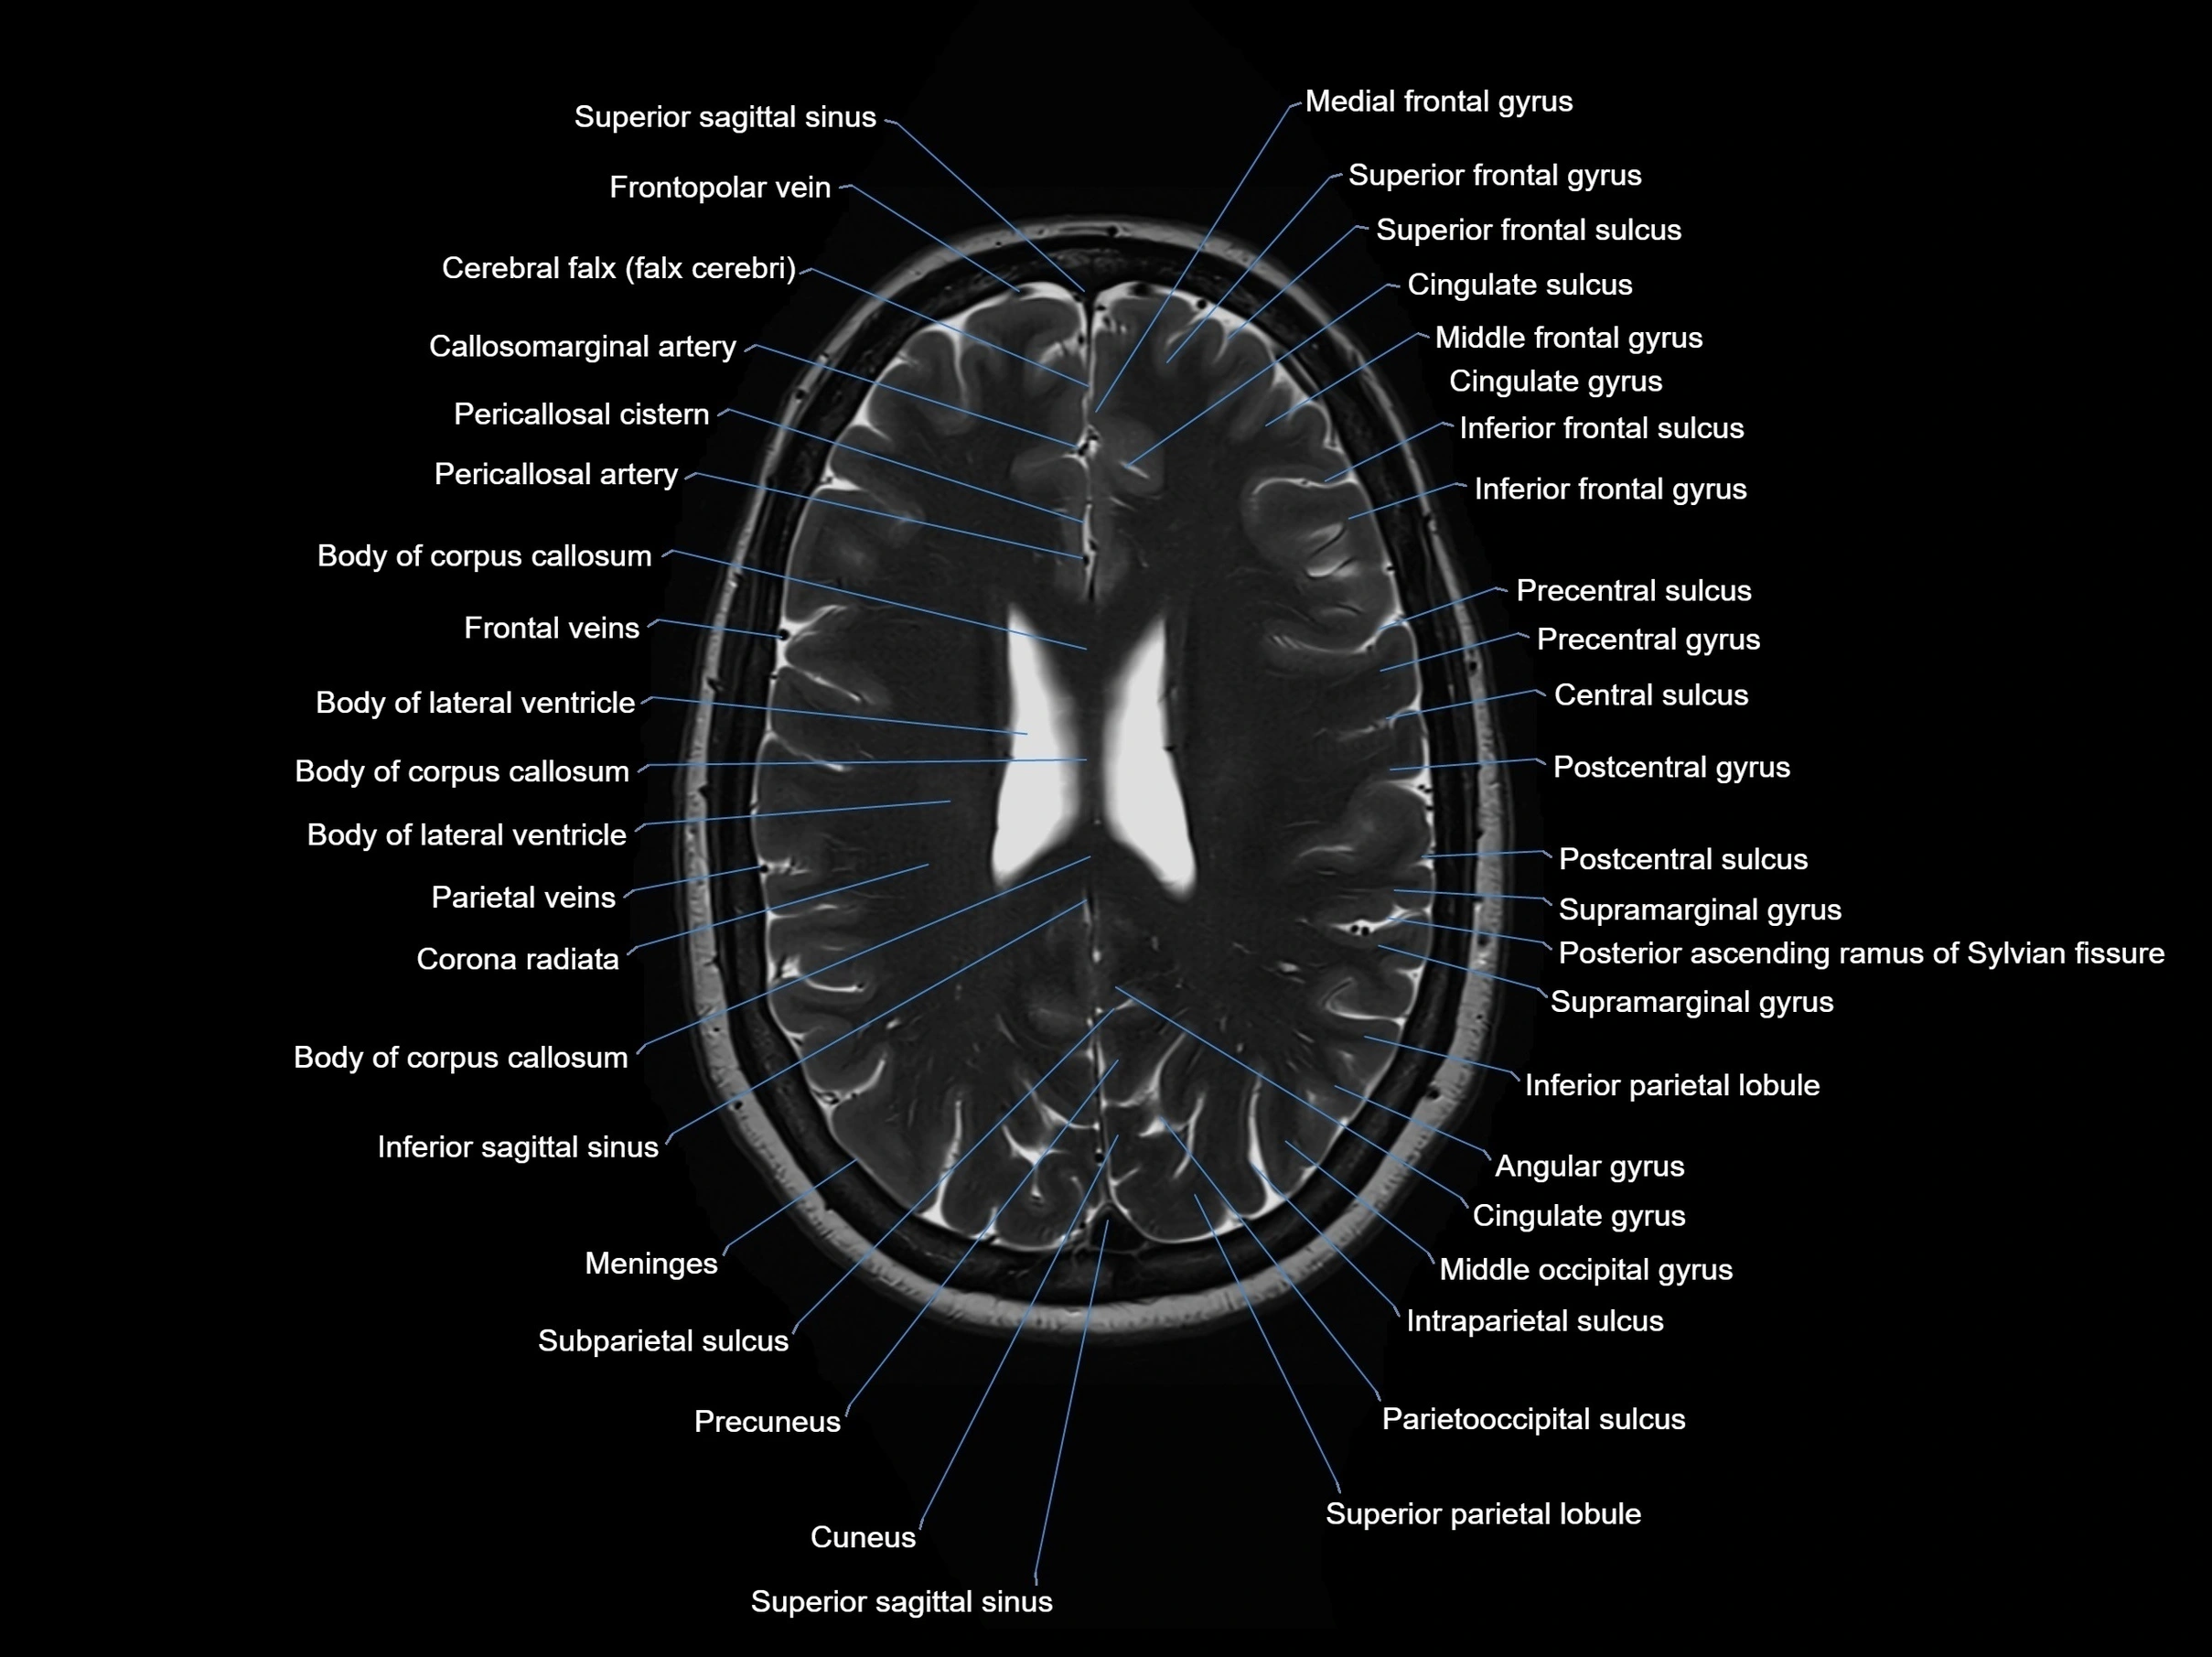

MRI images